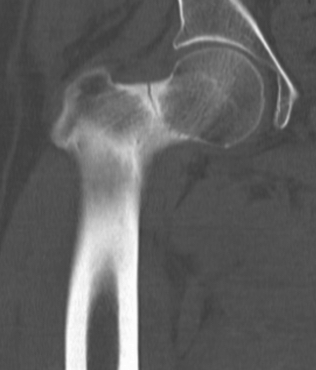

CT demonstrating incomplete fracture at inferior neck

CT demonstrate likely complete fracture, with some displacement